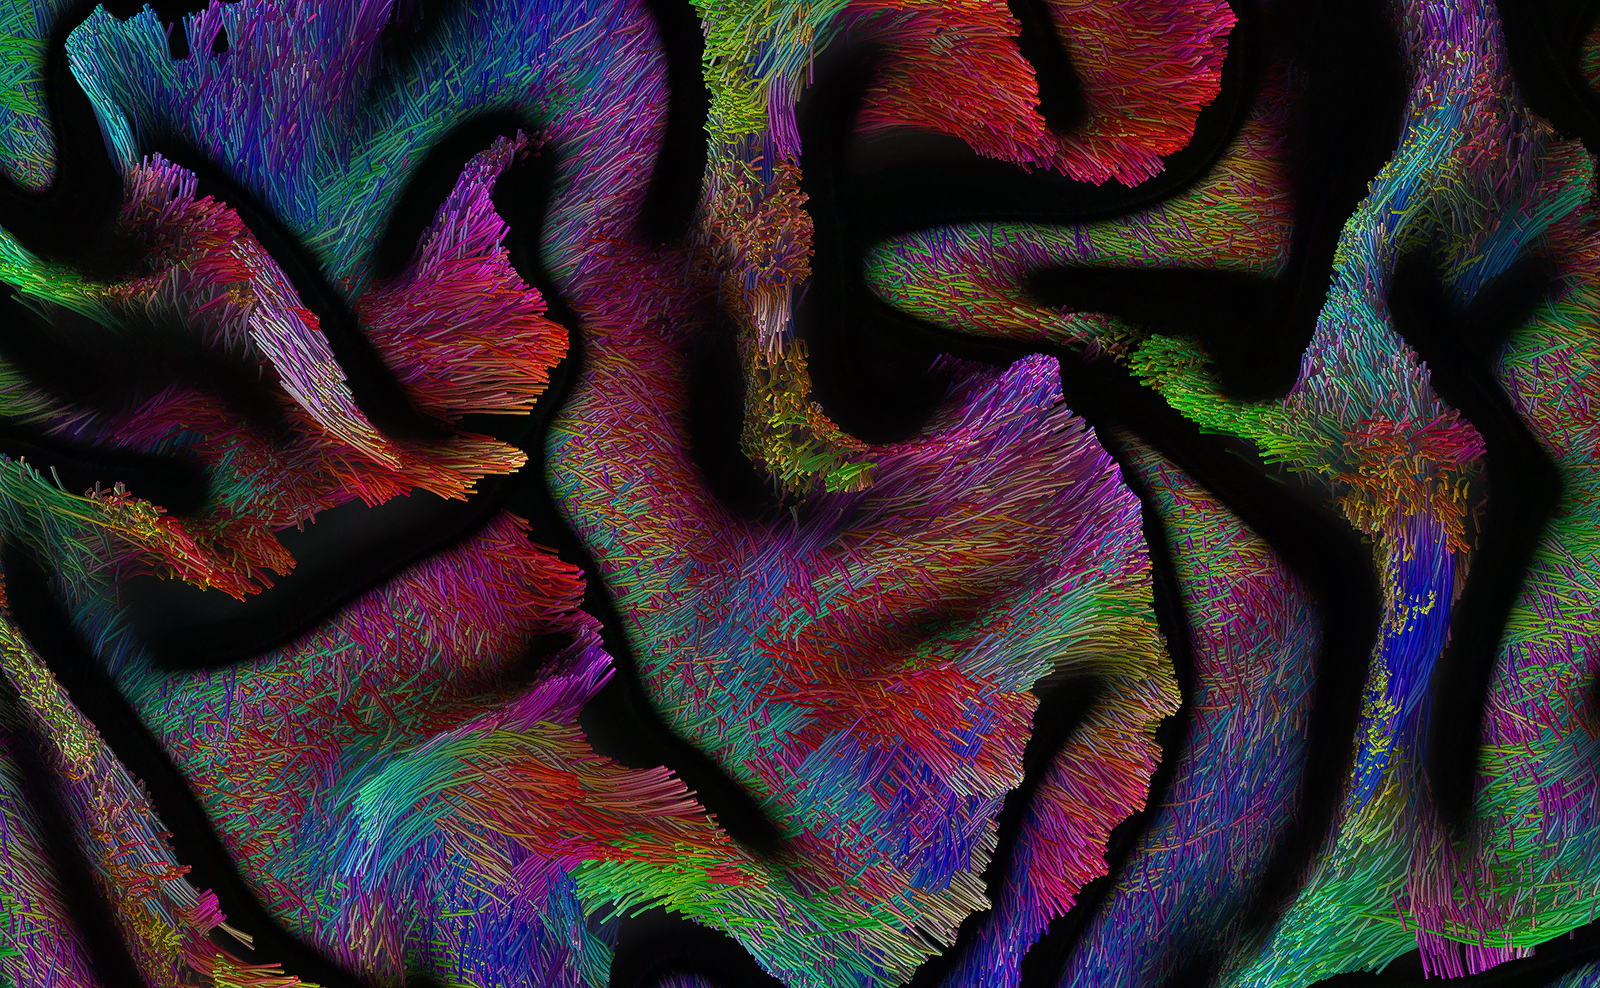

The Adaptive Digital Twin project aims to achieve their goals through four primary strategies. Firstly, we plan to implement a measure that allows real-time probing of effective local and widespread change in whole brain connectivity based on a combination of transcranial magnetic stimulation (TMS) and electroencephalography (EEG). Secondly, we generate high-quality neuroimaging data from brain tumor patients in a joined research project with DFG SPP 2041, which can be used to synthesize digital brain matter using machine-learning algorithms to dramatically increase cohort sizes. thirdly, we refine the correlation analyses of structure-function brain networks with psycholinguistic assessments and real-time mapping during awake surgery. Lastly, we model the effect of different lesions on the level of personalized biophysical brain network models by comparing patient profiles before and after their surgery along with their brain structure information.

In addition, in a further sub-project, we explore the material properties of the brain in relation to neuroimaging in tumor patients, investigating the effects of degeneration, pressure, or stretching mechanisms on brain tissues and the resulting functional consequences, in terms of network and behavior. We use MR-Elastography (MRE) imaging to measure local physical properties of brain matter and add a novel material science perspective to the question of the brain's structure-function relationship.